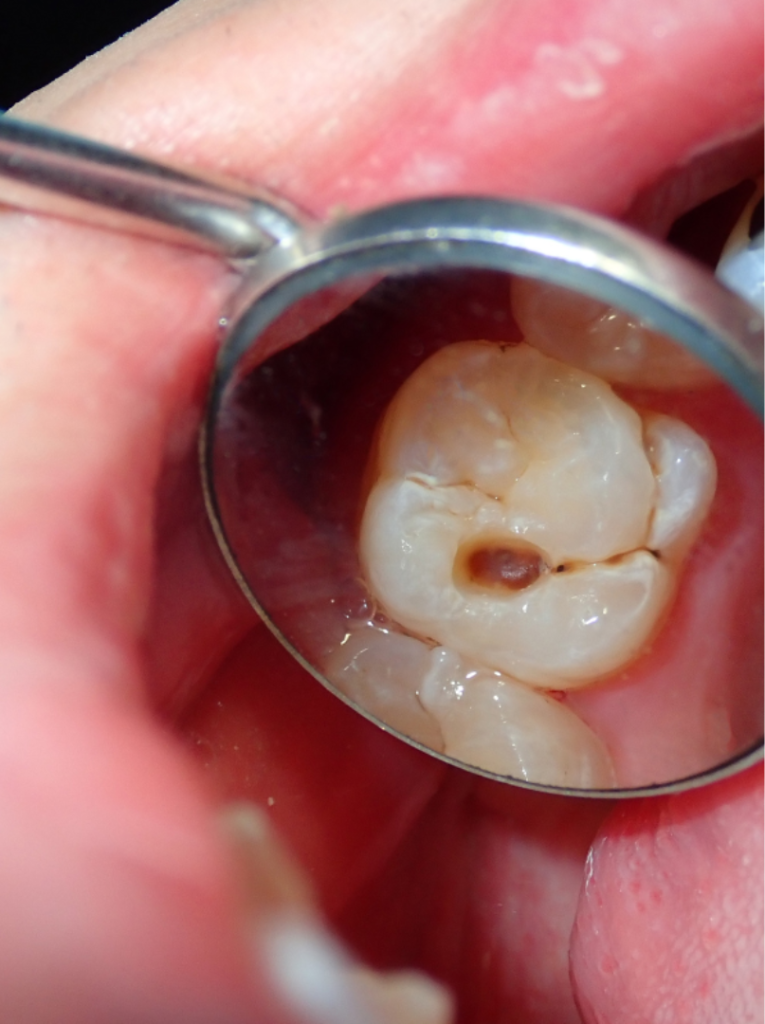

Common dental issues such as decay, cracks or trauma can eventually lead to infection of the pulp – the soft tissue at the core of the tooth. The pulp consists of connective tissue that performs several key functions:

When overwhelmed by bacteria, chemical or mechanical stimuli, the pulp becomes inflamed or infected. This is a condition known as pulpitis, which may progress to pulp necrosis (death of the pulp). When this happens, non-surgical root canal treatment is usually the first line of care to preserve the tooth.